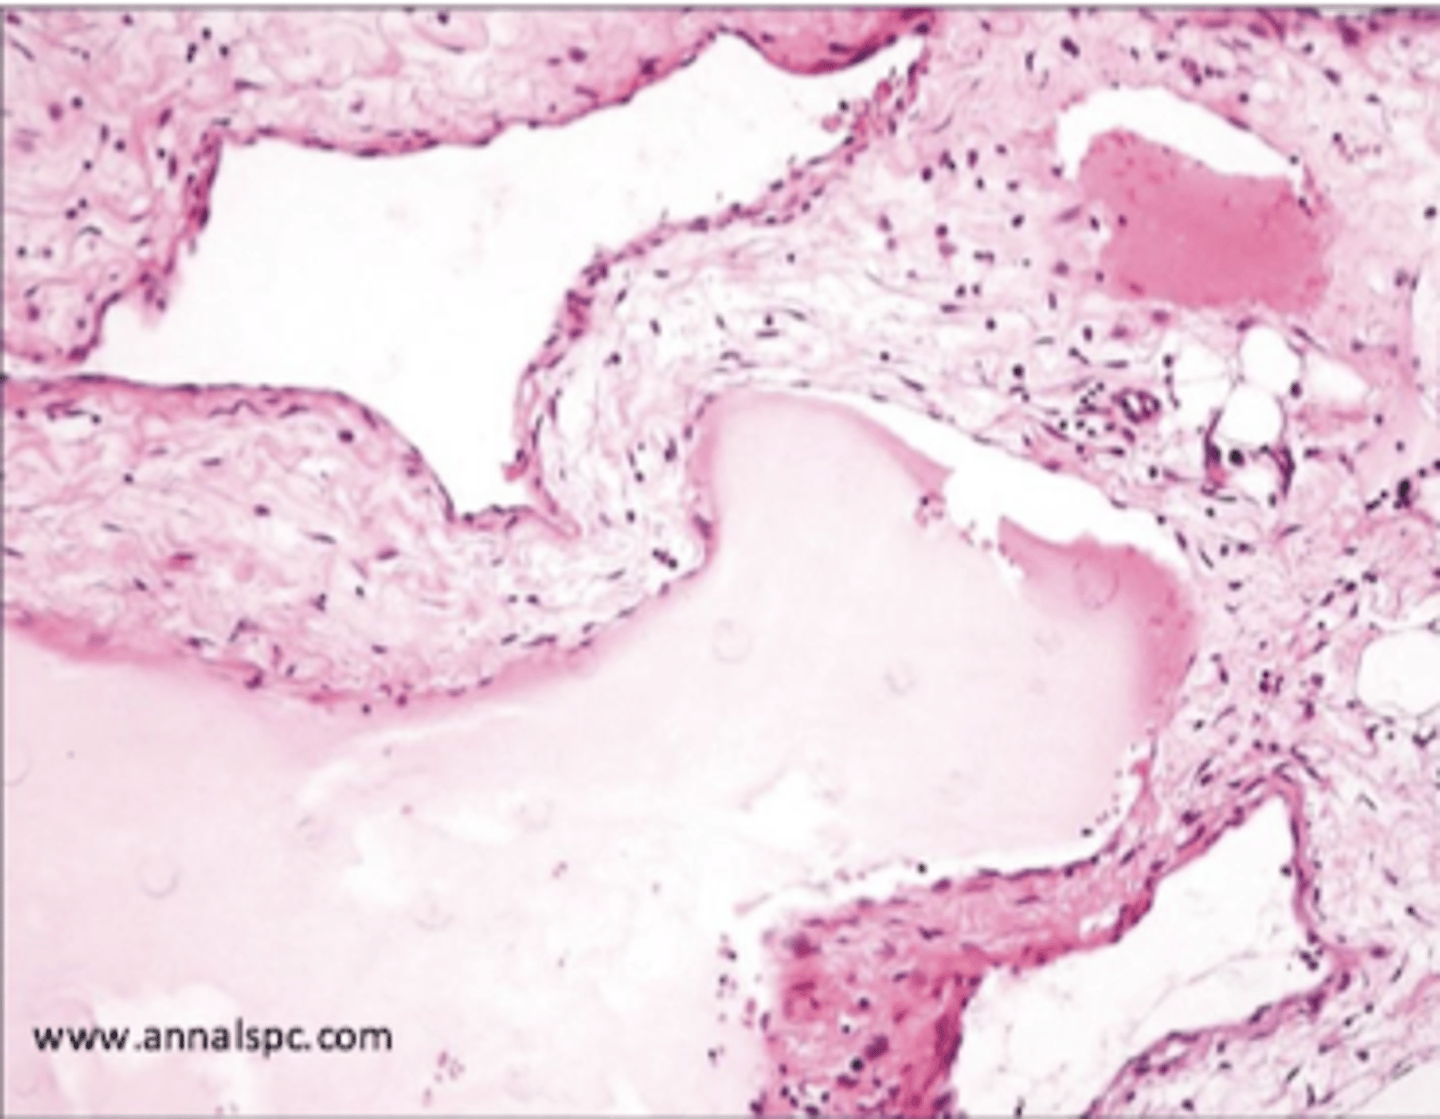

cavernous hemangioma

large blood filled dilated vascular changes with CT stroma

do not regress

cavernous lymphangioma

neck or axilla of children

massively dilated spaces with CT stroma and lymphoid aggregates